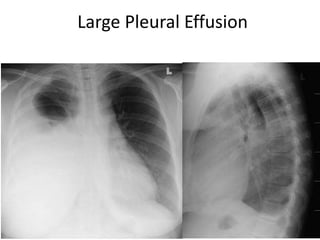

• Chest X-ray PA view showing dense

homogenous opacity at the Rt lung base with

curved upper border, blunting the

costophrenic angle and ascending towards the

axilla. Suggestive of Rt Pleural Effusion

• Around 200 mL of fluid is required in order for

it to be detectable on a PA chest X-ray.

Pleural Effusion

42

154 slides

Large Pleural Effusion